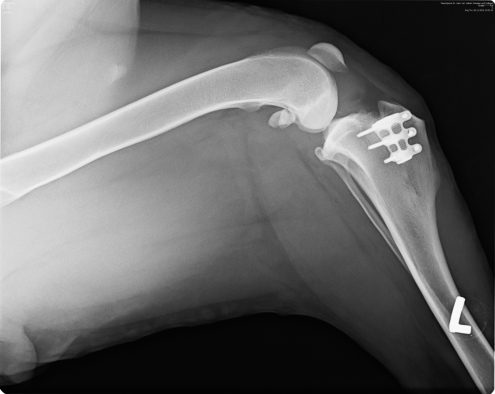

Das Implantat, das die inneren Kreuzbänder ersetzt, ist gut in Amélies Kmochen eingewachsen. Man merkt, dass es ihr langsam besser geht, die "Renneinheiten" werden wieder länger und ausgedehnter!